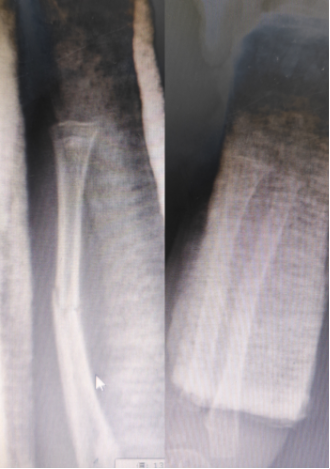

杜龙龙医生接诊后,仔细查阅患儿的病历与影像资料,又轻柔地为孩子进行体格检查。检查发现,患儿左前臂压痛显著,畸形突出,结合X线片显示的尺桡骨骨折断端移位、成角畸形等情况,诊断结果明确。考虑到陈旧性骨折因软组织粘连、骨痂已开始形成,手法复位难度远超新鲜骨折,加之患儿年龄较小,骨骼娇嫩脆弱,操作中稍有不慎便可能造成二次损伤。杜龙龙医生当即向董博主任和周健主任汇报病情,两位主任迅速赶到诊室,三人共同展开病情研判。为最大程度减轻孩子的痛苦,三位医生反复斟酌,制定了周密的复位方案,并向家属详细说明复位过程中的风险与预期效果,在取得家属知情同意后实施操作。

复位过程中,三位医生分工协作、配合默契。他们先轻柔按摩患儿前臂软组织,缓解肌肉紧张与粘连;随后通过持续牵引拉开骨折断端,为复位创造空间;最后精准运用折顶、旋转等专业手法,一步步纠正骨骼畸形。整个过程动作连贯、力度精准,仅数分钟便完成复位。复查X线片显示,骨折断端对位对线良好,患肢外观恢复正常。医生随即为患儿进行石膏固定,并详细指导家属观察血液循环、定期复查及早期功能锻炼等注意事项。董博主任特别叮嘱:“幼儿骨折愈合速度快,但陈旧性骨折的康复需要更密切的随访,我们会定期跟踪孩子的康复情况,及时调整护理方案,确保骨骼正常生长发育。”